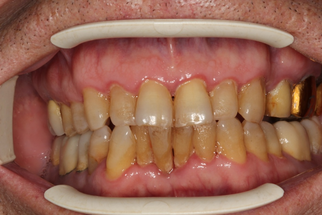

Через 30 дней после комплексного лечения с применением фотодинамической терапии у пациентов основной группы 3 отмечена выраженная положительная динамика состояния тканей пародонта по сравнению с исходным уровнем (Рисунок 15). Все пациенты отмечали снижение кровоточивости десен при чистке зубов, исчезновение неприятного запаха изо рта, гноетечения из ПК. Объективное обследование показало, что у всех пациентов отсутствовали признаки активного воспаления в тканях пародонта (отек и гиперемия), существенно снизилась степень кровоточивости десны, прекратилась активная экссудация из пародонтальных карманов.

| до лечения | через 30 дней после лечения |

| Рисунок 15. Динамика состояния тканей пародонта у пациента с ХГП тяжелой степени через 30 дней после комплексного консервативного лечения с применением фотодинамической терапии. | |